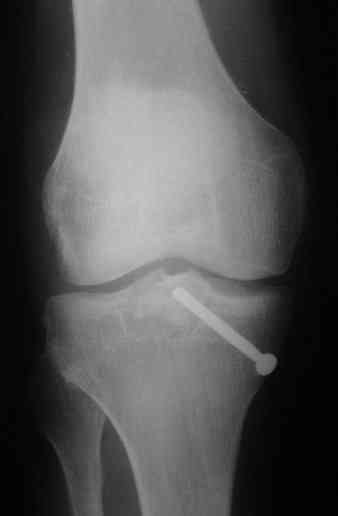

В 3 из 4 случаев мы применили винт, проведенный ретроградно по аналогии с фиксацией заднего края большеберцовой кости при переломах в

области голеностопного сустава. В прищепке рентгенограммы одного из наших пациентов до операции и спустя полгода. Остальные 3 наблюдения

описаны в статье "Изолированный отрывной перелом большеберцовой кости в месте прикрепления задней крестообразной связки // Вестник

травматологии и ортопедии им. Приорова. - 2001. - №1. – С. 38-40. Если есть интерес, могу прислать копию. Ваш случай, безуловно, отличается величиной костного фрагмента, его локализацией, характером и степенью смещения. Но думаю, принцип лечения может быть общим.

Операция из разряда травматологической "экзотики" прошла успешно. Доступ понравился:анатомичный, хорошая визуализация, удобно работать и оператору и ассистентам. Наложили пневможгут, но воспользовались им только на этапе ревизии сустава. Фрагмент развернулся на 90 град. на 2-ух "жгутах": медиально - сухожилие m.semitendinosus, латерально - задняя крестообразная связка. Мобилизовали,развернули и уложили на место без особого труда. Фиксировали отмоделированной 1/3-трубчатой пластиной. Мениск оказался неповрежден. Сустав стабилен. Обошлись без

иммобилизации, планируем начать ранние движения. Остальное на фото, дополнительно приложены корональные срезы КТ.